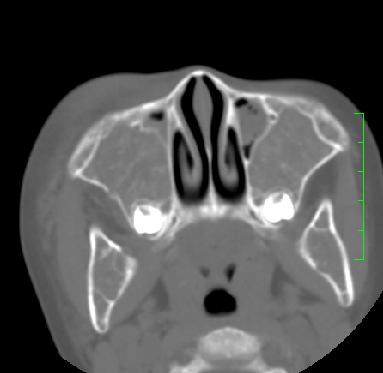

标题: PED1889:上颌窦病变

m,10y,外伤做ct